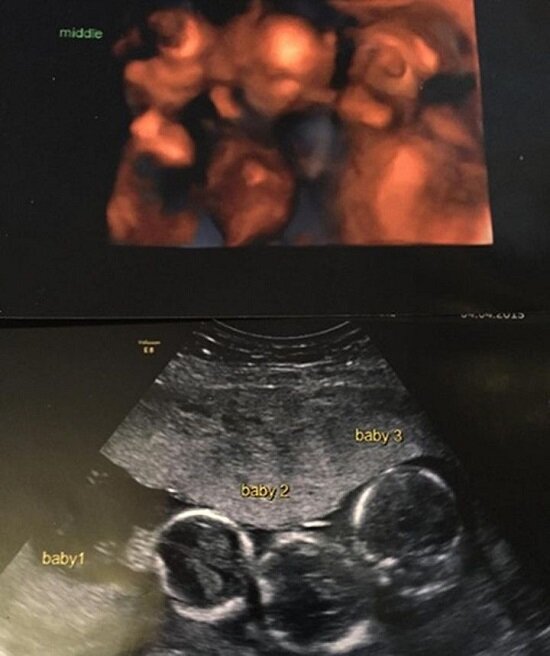

Pierwsze dwa miesiące nie były łatwe dla kobiety. Czuła się osłabiona, a częste nudności tylko pogarszały sprawę. Para postanowiła, że w trosce o dziecko wykona dodatkowe badania. Obawiali się ich wyników, które jednak zaskoczyły ich niezmiernie, lecz nie tym, ze były złe. Okazało się bowiem, ze w łonie kobiety biją aż trzy serca, a nie jedno. Oboje byli w szoku. W ich rodzinach nie trafiały się wcześniej mnogie ciąże.

Czas mijał szybko, zdrowie Becky-Jo się poprawiało, a ciąża przebiegała prawidłowo. Wszystko szło dobrze aż do 31 tygodnia ciąży. Zakończono ją cesarskim cięciem, a na świat przyszło trzech delikatnych i drobnych chłopców – Rocco, Rohan i Roman. Każdy z nich ważyło po ok. 1,5 kg. Kolejnych 6 tygodni chłopcy spędzili w inkubatorach, ale gdy tylko nabrali odporności i odpowiedniej wagi lekarze pozwolili zabrać ich do domu.